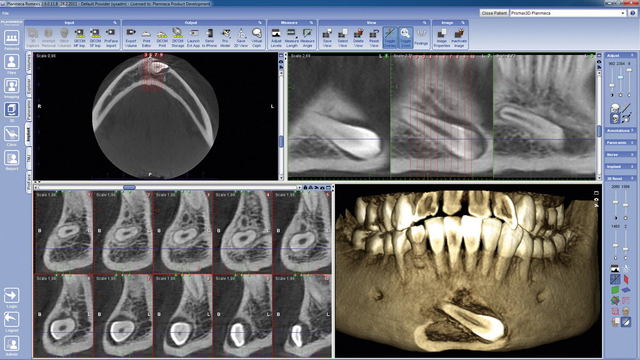

(TCHC –Tomógrafo Computerizado de Haz Cónico–, o CBCT –Cone Beam Computed Tomography, Europa (1997-1999)

Introducidas a raíz de los trabajos elaborados en el Proyecto Phidias